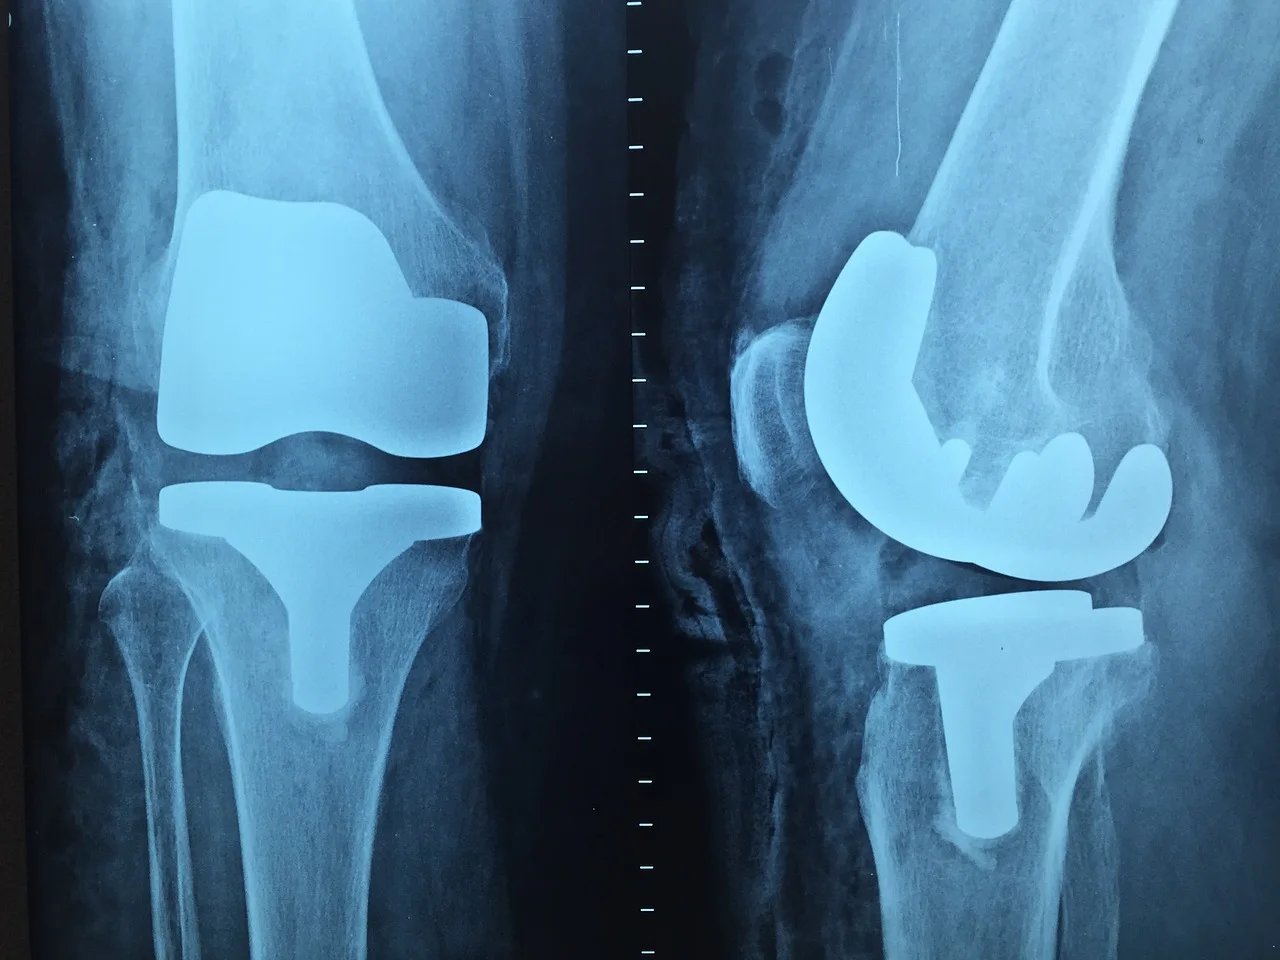

A knee replacement is a surgical procedure that involves removing the ends of the bones that form your knee joint and replacing them with a prosthetic device. Most often, a knee replacement is performed because arthritis has developed within the knee joint, which causes common activities to become difficult and painful. The new prosthesis creates a smooth joint surface which, after recovery, allows you to return to pain-free activities.

The knee joint is made up of three different compartments: the medial knee compartment, the lateral knee compartment, and the patellofemoral compartment. In a total knee replacement, the surgeon replaces all three compartments of the knee. With a partial knee replacement, the surgeon is replacing only one compartment, which is why another name for a partial knee replacement is a unicompartmental knee replacement.

With a total knee replacement, the surgeon will remove the bottom of your femur (thigh bone), the top of your tibia (shin bone), and the back of your patella (knee cap). They will also remove your ACL and PCL, which are ligaments in your knee joint, and all of this will be replaced with a metal and plastic implant. The exact materials of the metal and plastic can vary, so I suggest asking your surgeon if you’re curious what your new knee is made out of.

With a partial knee replacement the most common compartment that is replaced is the medial knee compartment. This is because the medial knee compartment is usually more severely affected by arthritis. The ACL and PCL are usually left intact with a partial knee replacement. However, if the ACL is not able to be salvaged, then the surgeon will use a slightly different implant to accommodate for this.